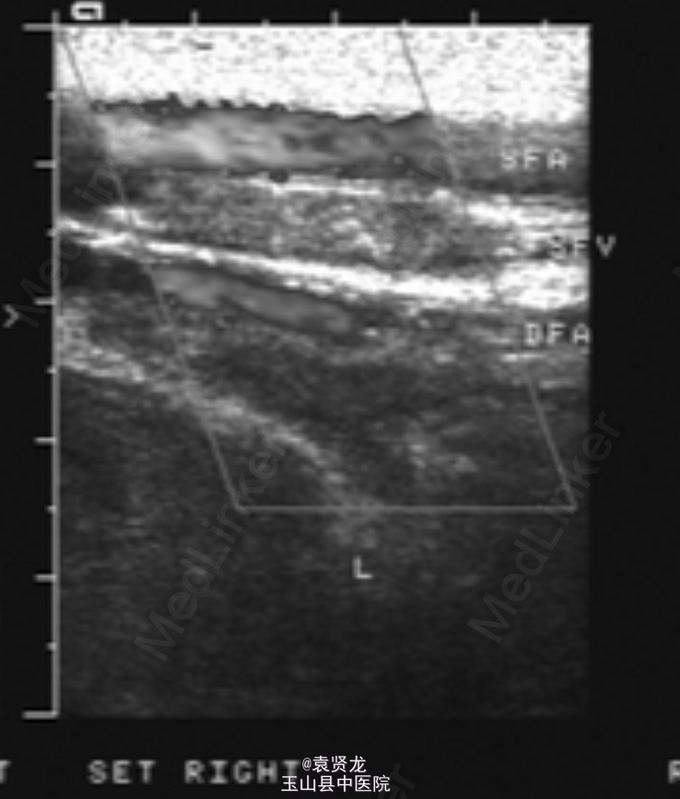

体温37.5°C,一般情况可,贫血貌,皮肤黏膜未见瘀点及出血点,浅表淋巴结未触及,胸骨轻压痛,双肺呼吸音清,可闻及少量湿性啰音。心律齐,各瓣膜听诊区未闻及杂音。肝脾肋下未触及。左下肢肿胀,皮温不高,伴有压痛,左 膝关节活动受限。神经系统检查未见异常。胸片:双上肺肺结核浸润影。髋 关节正侧位片无异常。血常规:WBC 10. 6*10^9/L,Hb78L,P1t 53*10 ^9/L,左下肢深静脉彩超示:左下肢深静脉及大隐静脉近心段血栓形成。骨髓象:骨髓增生明显活跃,粒:红= 0.28:1,原幼占39%,分类不明细胞占57%,胞体大小形状不一,胞核可见扭曲、折迭、切迹,核仁 1~3个。

诊断AML伴左下肢深静脉血栓。给予抗结核、对症止痛 、纠正贫血治疗,爱脉朗口服+华法林1片(1/d) ,并监测凝血功能。1周后,患者症状减轻,予DA化疗方案。